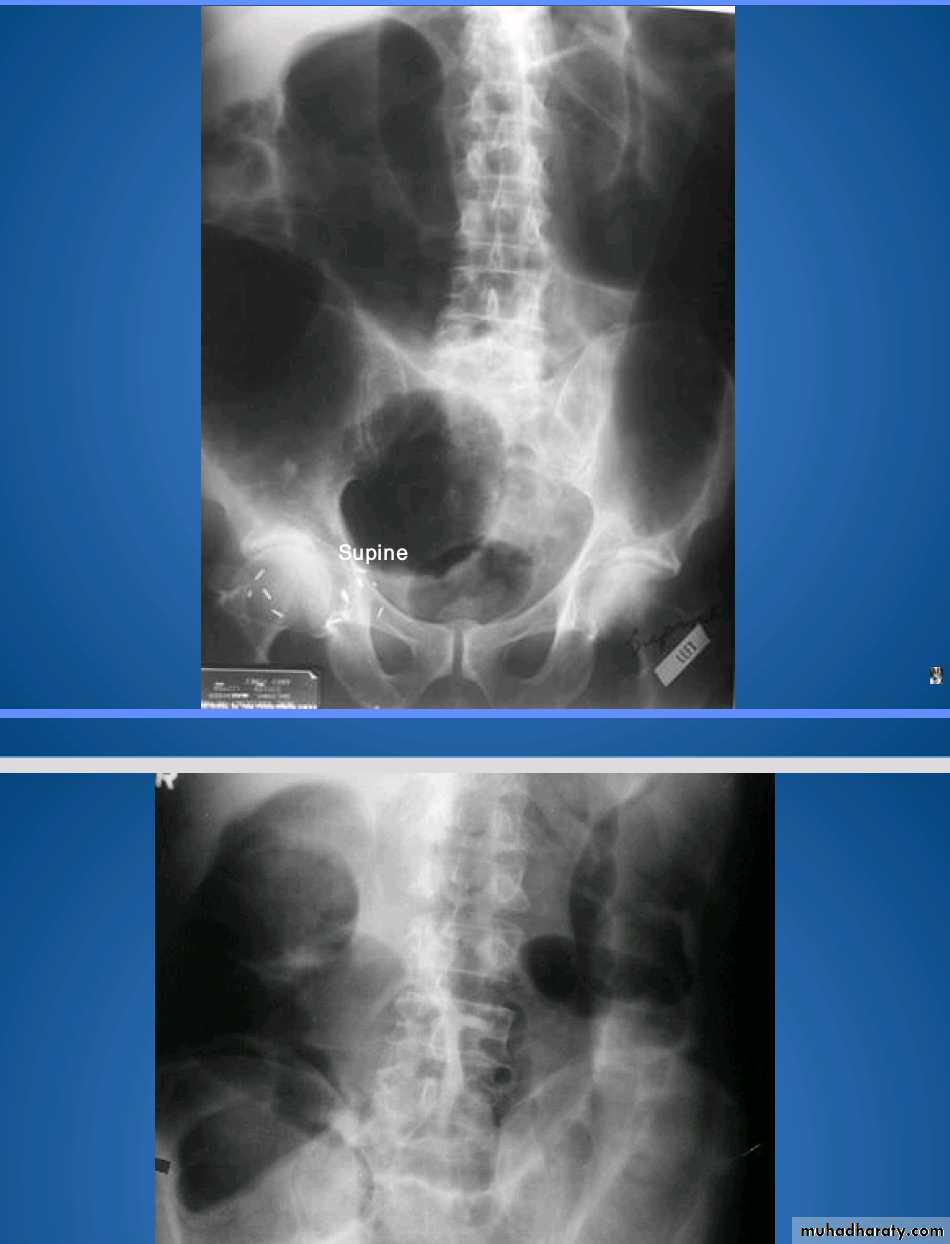

Small bowel obstruction accounts for 80% all mechanical intestinal obstruction; the remaining 20% result from large bowel obstruction

Radiographic features

Abdominal radiograph

Abdominal radiographs are only 50-60% sensitive for small bowel obstruction .

In most cases, the abdominal radiograph will have the following features:

dilated loops of small bowel proximal to the obstruction

predominantly central dilated loops

three instances of dilatation over 3 cm

valvulae conniventes are visible

fluid levels if the study in erect position